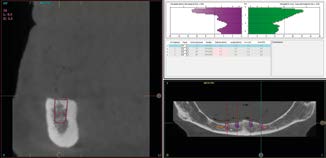

Trước khi bắt đầu quy trình cấy ghép Implant ngắn 6.5mm BTI, tất cả bệnh nhân tiêu xương dọc đều trải qua quy trình chẩn đoán toàn diện, bao gồm chụp cắt lớp vi tính chóp nón (CBCT), mẫu hàm nghiên cứu và sáp chẩn đoán (diagnostic wax-ups). Phân tích 3D của phần xương còn lại giúp xác định vị trí, góc độ và đường kính Implant một cách chính xác.

Các Implant ngắn 6.5mm BTI được đặt bằng cách sử dụng quy trình khoan định hướng sinh học (biologically guided drilling protocol) độc quyền của BTI, với lực vặn chèn được đo tại thời điểm đặt để xác nhận sự phù hợp cho việc chịu lực tức thì. Các phục hình tạm thời liên kết bắt vít được gắn ngay sau phẫu thuật để ổn định sự phân bố lực trong quá trình tích hợp xương. Từ 3 đến 6 tháng sau, chúng sẽ được thay thế bằng các cầu răng sứ kim loại cố định hoặc phục hình lai kim loại-nhựa, đảm bảo phục hình hoàn hảo cho bệnh nhân tiêu xương dọc.

3.2. Lên kế hoạch mô phỏng và ứng dụng Implant ngắn 6.5mm BTI